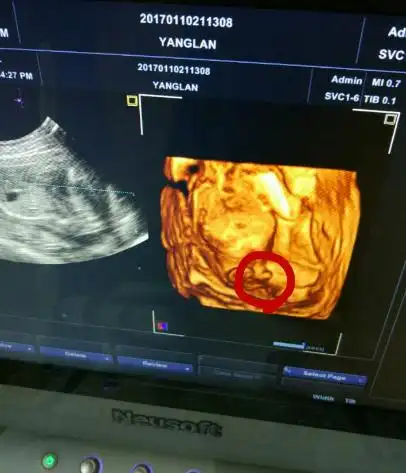

四维彩超,两次发现貌似蛋蛋的两个对称的东西,中间间隔几分钟,再看